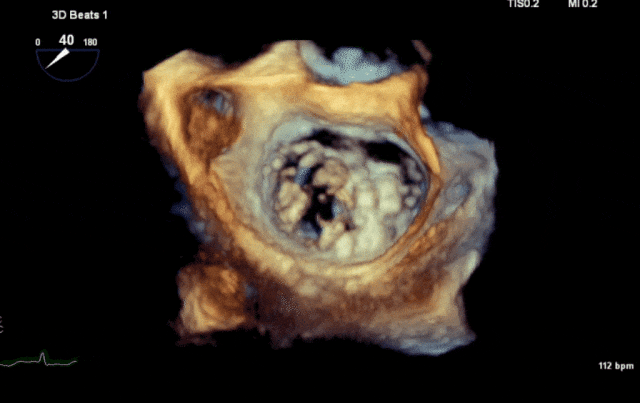

心脏超声示左室增大,二尖瓣2、3区脱垂伴重度反流(腱索断裂),Carpentier分型Ⅱ型,典型Barlow综合征表现;二尖瓣开放面积5.0cm²,3区瓣环内径31mm,前叶长22mm、后叶17mm,前叶收缩期关闭瓣体部分呈拱形突向左房腔,瓣膜游离缘对合欠佳,可见腱索断裂,长度9mm;2区瓣环内径32mm,前叶长22mm、后叶10mm,前后叶均可脱垂;三尖瓣重度反流。CDFI示瓣口重度偏心性反流,反流束沿主动脉后壁走行,肺静脉收缩期可见反向频谱。

术前瓣叶

术前3D